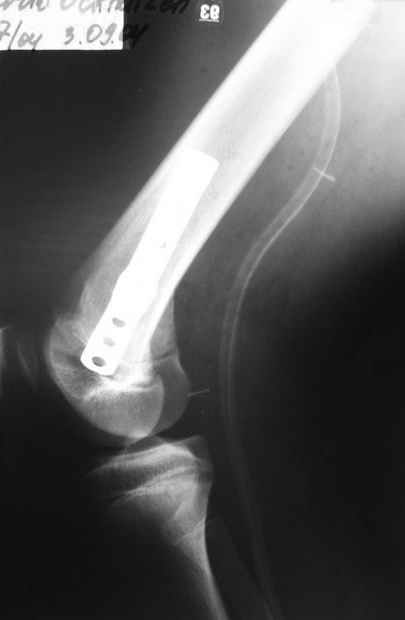

Как вариант решения прогрессирующей вальгусной деформации коленного сустава я бы предложил косую остеотомию дистального отдела бедра с фиксацией пластиной и компрессирующим винтом.

Взгляните на снимки , может быть это вам поможет.

Около 5 лет применяю этот тип дистальной остеотомии бедра для коррекции механической оси Н/К ( более 20 случаев) - достаточно эффективная операция.

Было одно осложнение у молодого пациента - ятрогенное повреждение бедренной артрерии, которое решилось васкулярной пластикой без каких -либо последствий для функции конечности.

- Конечно, другая: я применял этот тип остеотомии при различных состояниях, приводящих к деформации механической оси сустава, но техника её тандартна,

расчеты индивидуальные.

-Деформация оси сустава может быть варусной или вальгусной, причины - структурные изменения в латеральном -или медиальном отделе сустава (переломы, патология зон роста, дисплазии, дегенеративные процессы) результат лечения внутри- или внесуставного перелома и восстановление оси обуславливается анатомичностью репозиции и адекватностью фиксации. Нередко в запущенных -неправильно срасшихся unicompartmental внутрисуставных переломах восстановление оси и опороспособности достигается периартикулярными

остеотомиями...